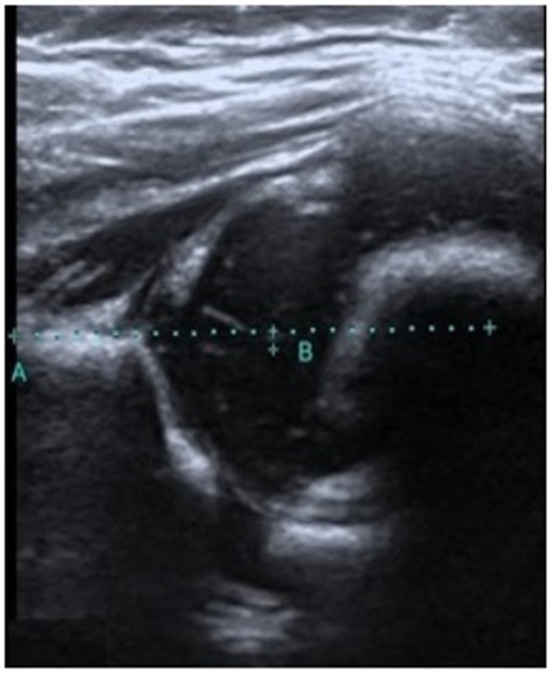

As a result of our detailed literature search, it is apparent that there has been no previous study on the measurement of the medialization of the femoral head. However, Kosar et al. performed a remarkable similar study evaluating the medialization of the acetabular roof. The aim of this study by Kosar et al. was to evaluate the correlation between acetabular roof medialization and the prognosis of type 3 and type 4 hip treatment. A total of 35 hips were evaluated in this study. As a result of their study, they reported a strong correlation between acetabular roof medialization and prognosis [16]. In our study, FMD measurement was used to differentiate between type 1 and type 2 hips and a statistically significant difference was found. Future research may differentiate between type 1 and type 2 hips using acetabular roof medialization. Furthermore, given the findings of Kosar et al. [15] on the advantageous effects of acetabular roof medialization measurement for treatment, future studies on type 2 hip diseases may yield more reliable results. Further investigation of the correlation between alpha and beta angles and the FMD in future studies may provide more reliable findings. In our study group, in a 60-day-old infant diagnosed with an immature hip by the Graf method, the FMD medial values showed results supporting this diagnosis (Figure 3).

Figure 3. Alpha angle of 58 and beta angle of 55 measured in a 60-day-old type 2 physiological immature hip; the FMD value measured 2.1 mm (FMD refers to the distance that remains between point B and the decussated A line, which is drawn parallel to the femur from the iliac bone. Point B refers to the center of the femoral head).